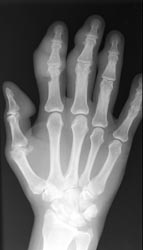

While all of the compartments of the hand and wrist are susceptible, the carpometacarpal and intercarpal joints are the most frequently involved. Asymmetric distribution is characteristic of gouty arthritis.

Periarticular soft tissue swelling may be the first radiographic sign of an acute gouty attack. Soft tissue sodium urate deposits can occur with chronic gout which creates a dense mass called a tophus that can occasionally contain calcifications. This distribution is random and is usually seen on the dorsal surfaces. Osseous erosions are periarticular with sharp sclerotic margins and an asymmetric distribution. Overhanging edges with a well-defined osseous shelf at the erosive site can sometimes be seen. Loss of normal bone mineralization is not a characteristic finding of gout and if present, the osteoporotic findings are mild. Joint space narrowing does not usually present except in more advanced stages.